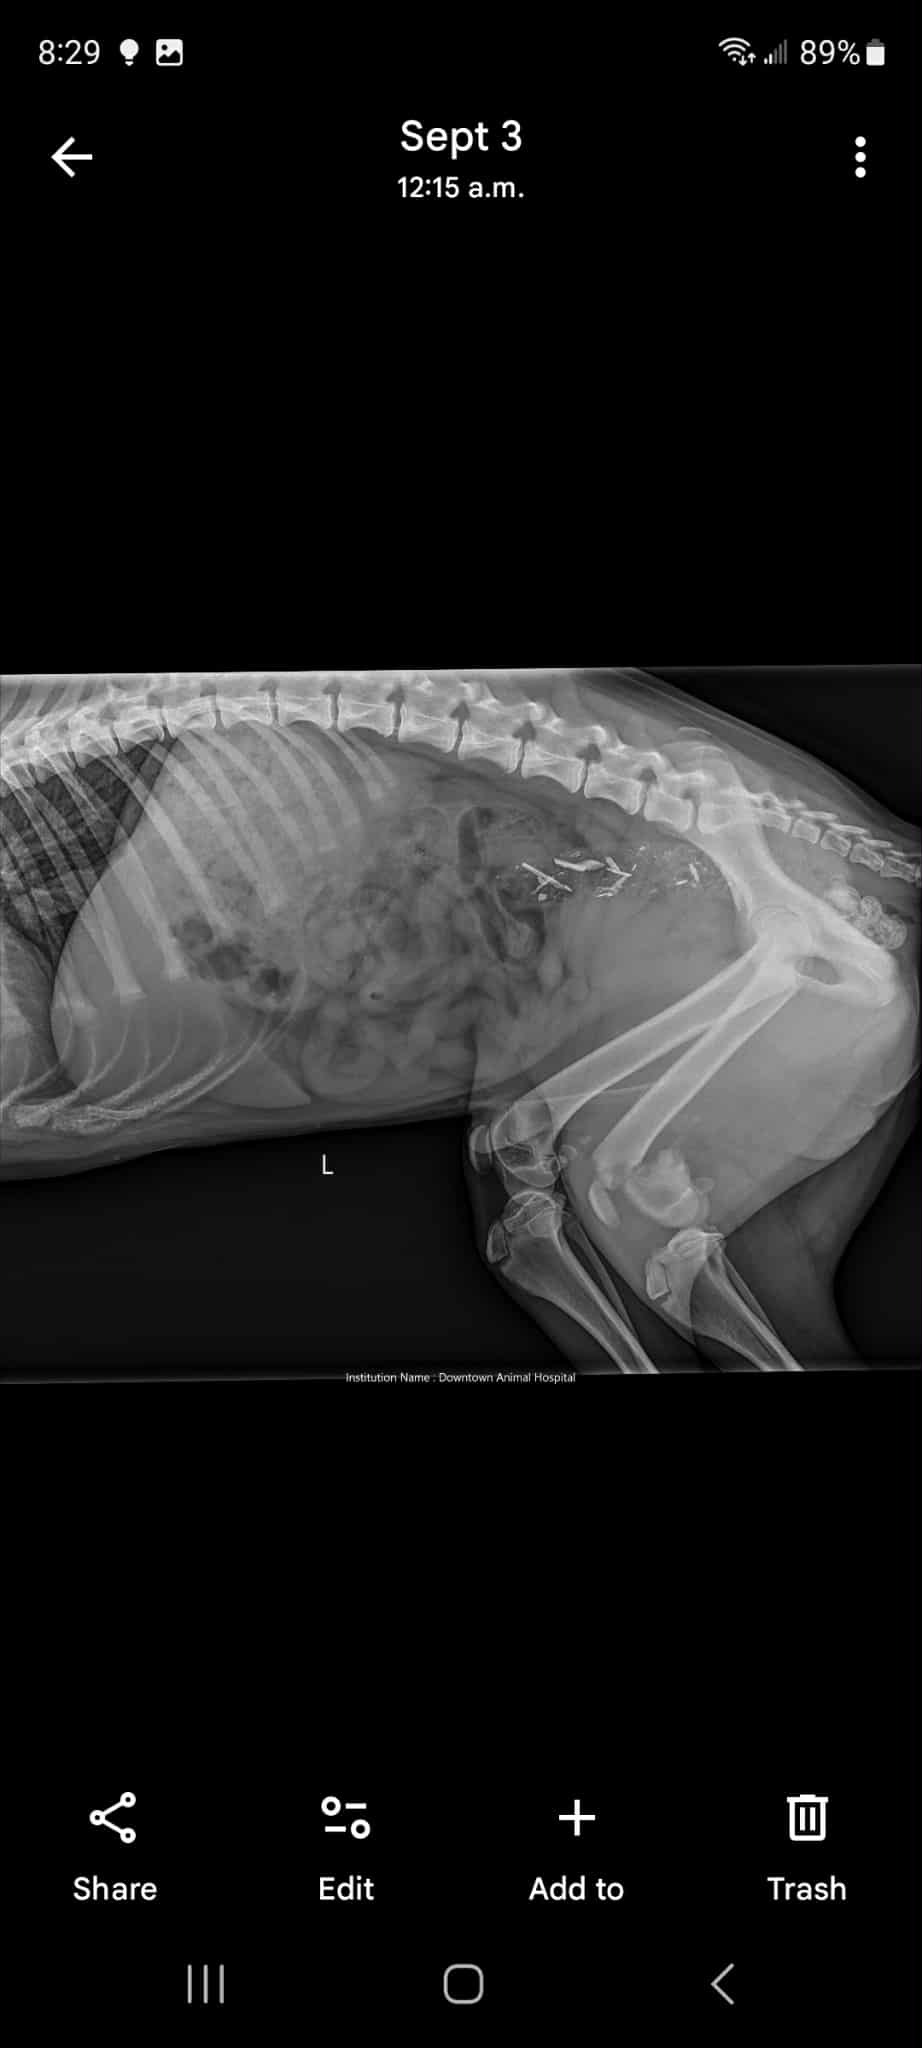

After numerous strokes left his father paralyzed Donald and his partner Missy needed to do major renovations on their home. Which was a huge financial burden that is still effecting them to this day. Their dog Joe is still just a puppy. But is currently in training to play a very important role in their lives. Donalds father has suffered over 2,000 strokes which can come on at any time. Missy, Joe's mom, also has epilepsy. He's not just a pet, he assists them in their daily lives. On Thursday an Amazon delivery driver who was unknown to them struck Joe. Thankfully no internal organs were damaged. Most of the injuries he suffered were to his leg. Joes tendons that are meant to hold his knee together are completely irreparable. The nerve endings have all been severed. His bones are broken and there's no blood flow. So it's basically dying from the knee down and needs to be removed. The estimated cost is approximately up to $7,000 or more, depending on factors that may come into play during the procedure. Amazon has been contacted. But unfortunately there were no other witnesses at the time of the incident. So the family has been left to cover the expenses. If you could please help by sharing this post or by donating anything you're able to. Joe is still young and deserves to walk and live a life without this damage. We really appreciate all the help we can get.